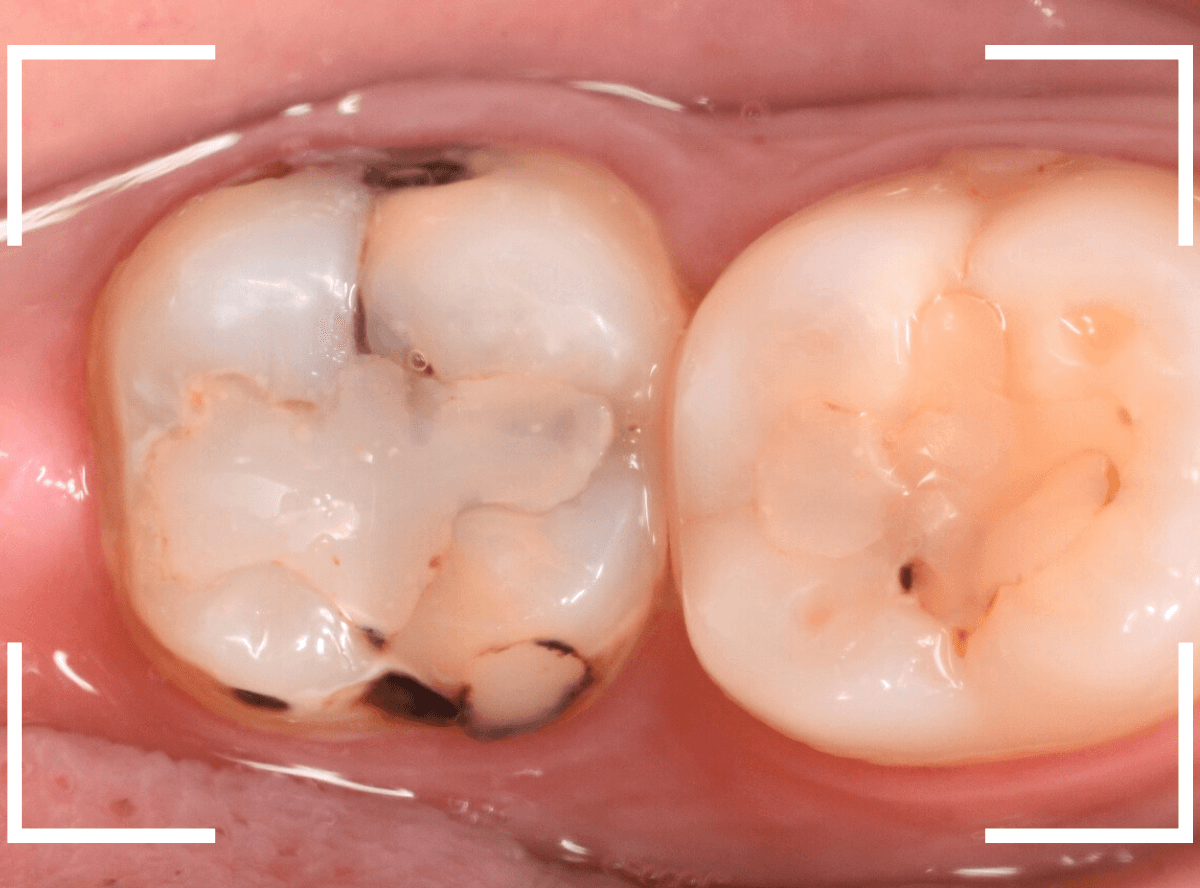

Case.8 大きな虫歯なのに、レントゲンではっきり写らない

こちらも定期検診希望で来院された患者さんです。

お口の中を拝見すると、明らかに虫歯がありました。

3本虫歯になっており、特に中央の小臼歯はかなり大きな虫歯になっているのが予想されます。

治療前にレントゲン写真で虫歯の大きさを確認するつもりが・・・あまりはっきり写ってきません。

患者さんに状況を説明して、歯を少しずつ削りながら虫歯を確認する事になりました。